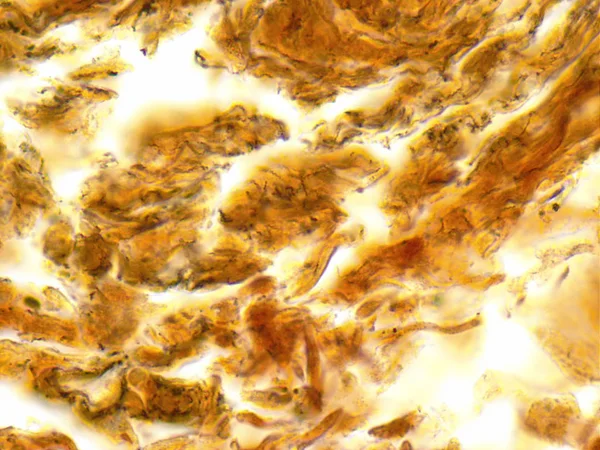

Siphilis adalah sebuah infeksi sistemik yang disebabkan oleh treponem…

Siphilis adalah sebuah infeksi sistemik yang disebabkan oleh treponem…

Siphilis adalah sebuah infeksi sistemik yang disebabkan oleh treponem…

Siphilis adalah sebuah infeksi sistemik yang disebabkan oleh treponem…